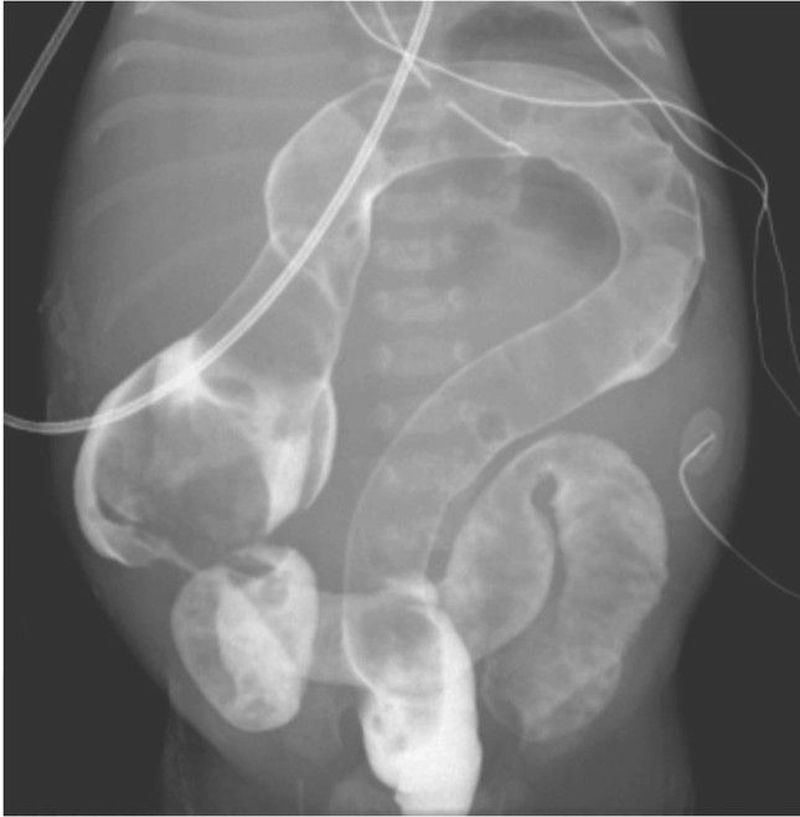

A baby boy born at 39 weeks of gestation to a 28-year-old woman had bilious emesis, failure to pass meconium, and abdominal distention within 24 hours after birth. Abdominal radiography revealed dilated bowel, a finding consistent with a distal obstruction. A water-soluble contrast enema showed a uniformly distended and shortened colon that appeared in the shape of a question mark, a finding consistent with total colonic aganglionosis. A specimen obtained at the bedside by transanal suction rectal biopsy had no ganglion cells found on hematoxylin and eosin staining, a negative result on calretinin staining, and abnormally thickened nerve fibers. These findings confirmed the diagnosis of Hirschsprung’s disease, a congenital absence of enteric ganglion cells resulting in a loss of bowel motility in affected areas. The patient was taken to the operating room, where laparoscopic serial frozen-section biopsy specimens of the entire colon were obtained and no ganglion cells were identified. Abundant ganglion cells were found at the level of the terminal ileum, and an end ileostomy was performed. Six months later, the patient underwent a colectomy with stapled side-to-side anastomosis of the terminal ileum to the rectal remnant (Duhamel procedure). At the postoperative visit, the infant was having five to eight bowel movements daily and was growing well.